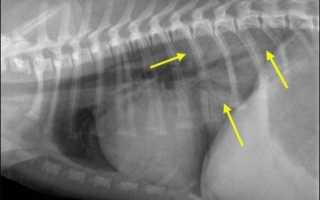

При всех формах отека легких главным диагностическим тестом является грудная рентгенограмма. Грудная рентгенограмма подтверждает или опровергает наличие жидкости в легких (затемнение легочных полей с одной или обеих сторон), при сердечной патологии – увеличение в размерах тени сердца. Распределение инфильтратов может помочь в определении этиологии. В человеческой медицине давление заклинивания в лёгочных капиллярах (ДЗЛК) является золотым стандартом для дифференцировки кардиогенного от некардиогенного отека легких, но в ветеринарии применяется очень редко, так как для его измерения необходимо установить катетер в легочную артерию.

рис. 1 — отек

рис. 2 — норма

У собак с кардиогенным отеком грудная рентгенограмма документирует кардиомегалию, венозный застой, интерстициальную и альвеолярную инфильтрацию. У собак инфильтрация обычно начинается в перихилярной области (корень легкого), но может расширяться и в тяжелых случаях поражать всю паренхиму легкого. У кошек с кардиогенным отеком на рентгене так же можно увидеть кардиомегалию, застой в легочных венах, но картина отека вариабельна.Также желательно проводить следующие исследования: эхокардиография, ЭКГ, измерение ДЗЛК.

У животных с некардиогенным отеком грудная рентгенограмма покажет инфильтрацию паренхимы легких без кардиомегалии. Другие диагностические тесты: нормальная эхокардиограмма и нормальное ДЗЛК.